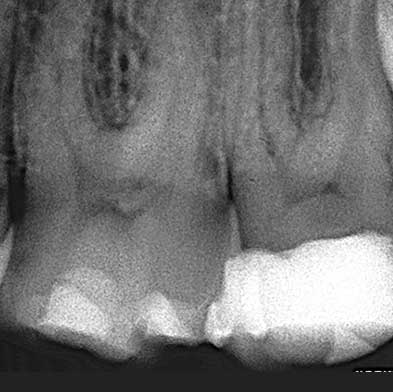

Endodoncia

Dra. Carmen Feito Bárcena